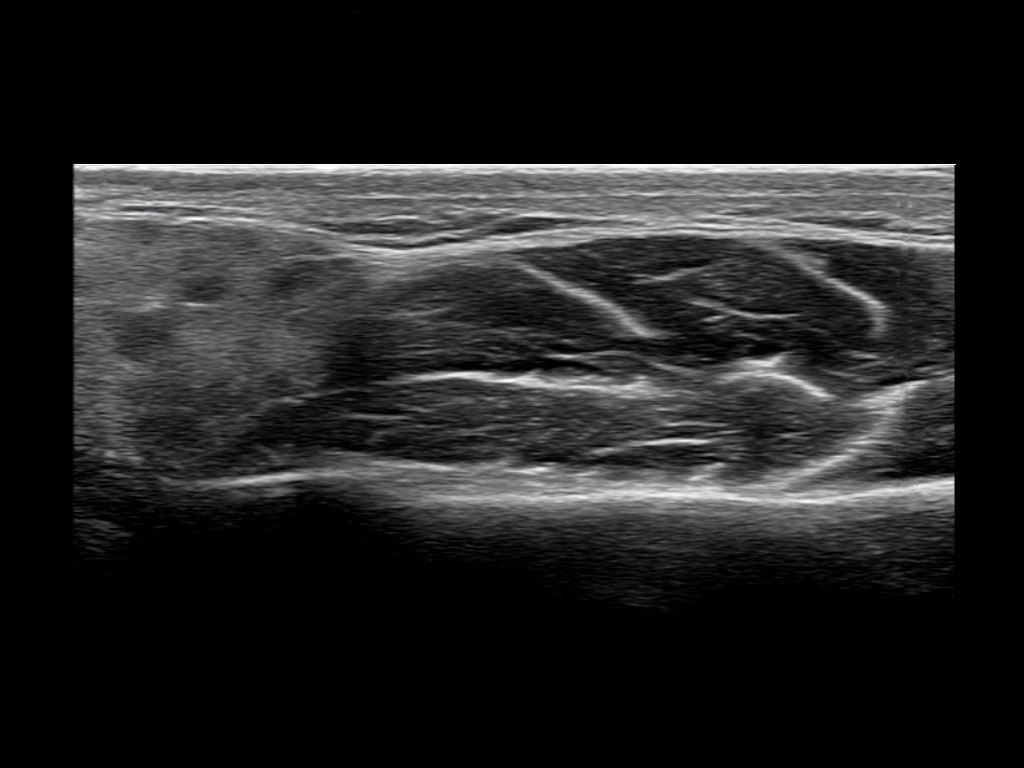

Filler injections in the parotid gland may go unnoticed, however, inflammatory reactions and abscesses may occur. Hypervascularity can be seen with color doppler. Filler deposits are supposed to be injected into the superficial fatty layer . The space to inject into this layer may be limited. Routinely we measure a width of 2-4 millimeters with sometimes subcutaneous layers being less than one millimeter thick.

Study the first image to recognize the different layers. If you are sure about the layers, swipe to the second image to view the answer (if applicable).